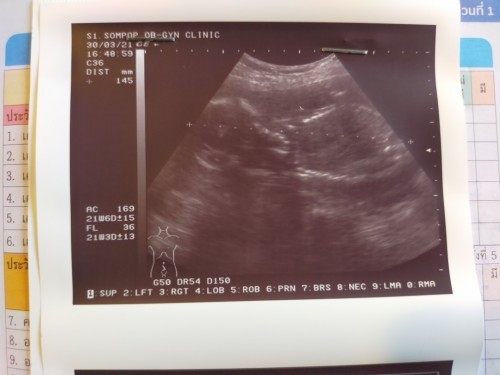

ลูกสาวค่ะ 21w